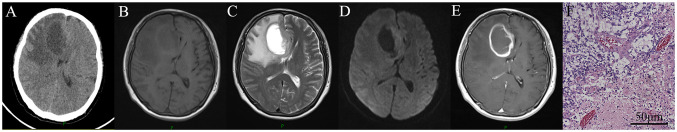

Cerebral glial tumors have become increasingly common in human immunodeficiency virus (HIV)-positive patients. The present study aimed to report a series of such cases, explore their clinical and pathological characteristics and subject all the reported cases to a survival analysis. The characteristics, management and prognosis of 10 HIV-positive patients with brain gliomas enrolled in a single hospital were investigated in detail. Immunohistochemical assessment of CD31, CD68 and CD163 was performed in the 10 HIV-positive patients with glioma and 18 HIV-negative patients with glioma. The relevant literature was also reviewed using relevant search terms. The potential predictive factors were screened by univariate and multivariate logistic regression analyses, and a nomogram was established based on the potential predictive factors. A total of 50 patients, including the 10 primary cases, were included in the survival analysis. The median survival time was 9 months. The gliomas of HIV-negative patients had a lower cell count of CD163+ cells than those of HIV-positive patients. High CD4+ T-cell count and the use of highly active antiretroviral therapy (HAART) tended to increase the median survival duration, although not significantly according to the log-rank analysis. In the univariate analysis, only surgery, radiotherapy (RT) and World Health Organization (WHO) tumor grade had significant associations with overall survival. In the multivariate analysis, only RT and WHO grade were independent predictors. In conclusion, gliomas may occur more frequently in HIV-positive populations than is currently recognized. The survival duration of most HIV-positive patients with glioma is determined by the tumor rather than HIV status. Adjuvant radiotherapy and the WHO grade of the glioma are predicted to be independent prognostic factors. Surgical resection followed by RT plus regular HAART is recommended for patients with glioma who are HIV-positive.